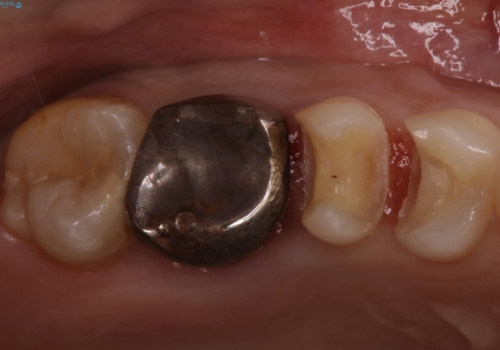

歯の間に食べ物がよく挟まるのを治したい

- 右上4、5間にフロスのひっかかりがあり、レントゲンから隣接面う蝕を確認しました。う蝕除去後は両歯にCADCAMインレーをセットしています。

歯の隣接面を正確に合わせることによって、物が詰まりにくく、再びう蝕になる確率を下げてくれます。